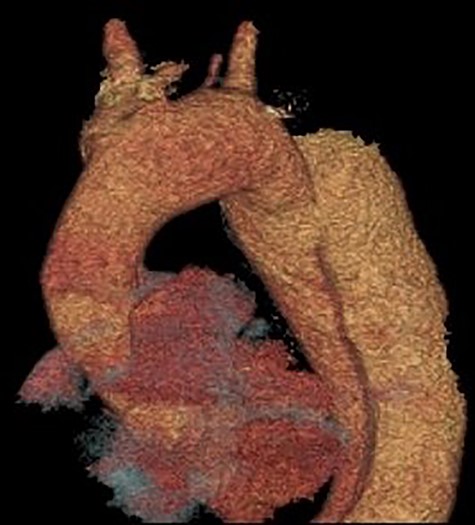

3D reconstruction of the CT scan demonstrating the four-vessel arch configuration with the aberrant left vertebral artery located in the Zone 2 region.

A 52-year-old gentleman presented to our institution with a previous history of TBAD (diagnosed 3 years previously), which was managed conservatively. His comorbidities included hypertension and excision of a left frontal cavernoma with no family history of aortic aneurysm or dissection. Following his initial presentation of chest pain, the patient had remained asymptomatic and stable. Surveillance management was initially instituted and the case discussed at the aortic multidisciplinary meeting. Due to retrograde extension of the TBAD into the distal arch, persistence of the false lumen, increasing descending aortic dimensions (6.0 cm) and an anomalous left vertebral artery originating from the aortic arch, the patient proceeded to aortic arch surgery and antegrade deployment of the stent into the descending aorta with a FET graft (Figs 1, 2). Preoperative coronary angiography and transoesophageal echocardiography revealed no coronary artery disease and a competent trileaflet aortic valve with preserved left ventricular function.

Our case demonstrates the successful use of FET for complicated TBAD as demonstrated previously [10]. The aberrant left vertebral artery originating directly from the aortic arch in the Zone 2 region is the most commonly observed variant, its incidence in a four-vessel epiaortic vessel configuration ranges from 0.68 to 5% [7]. Furthermore, an aberrant left vertebral artery is associated with a higher incidence of arterial dissection ranging from 0.9 to 1.9% [8]. Concerning aortic arch anomalies, the anatomical configuration of an aberrant left vertebral artery in the Zone 2 region pertains to challenging anatomy for TEVAR deployment. However, hybrid TEVAR with stent deployment into the conventional Zone 2 position and cervical transposition of the left vertebral artery to the left common carotid artery has been described [9]. Similarly, hybrid TEVAR with supra-aortic total debranching of the epiaortic vessels and cervical transposition of the left vertebral artery to the left common carotid artery with stent deployment into the Zone 2 position has also been reported [10]. Although not previously described, the surgical technique of reanastomosing the aberrant left vertebral artery to a Dacron graft and subsequent anastomosis to the perfusion limb of the Thoraflex graft mitigates the need for any concomitant cervical anastomosis of the aberrant left vertebral artery and favourably addresses this rare anatomical variation.